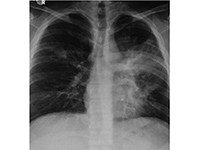

呼吸窘迫综合征【详细】

呼吸衰竭【详细】

重症肺炎【详细】